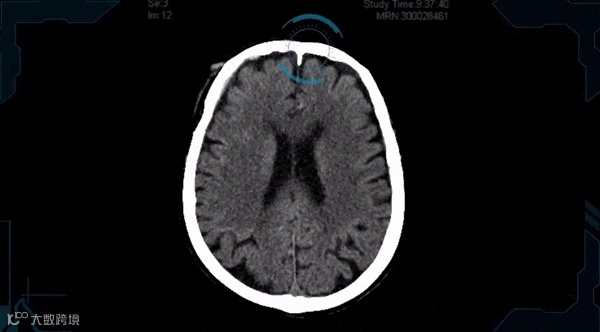

中风AI解决方案 Aidoc

影像医生每天需要看海量的片子,判断患者是否存在异常。如果发现了某些异常情况,他们便会将影像标记为“阳性”,并嘱咐患者做进一步的检查,这个过程通常会耗费大量的时间。以色列一家医疗科技公司开发了一系列能筛选异常影像的AI解决方案。比如他们针对中风开发的AI解决方案Aidoc,能快速连续识别异常缺血性和出血性中风影像,并将可疑病例自动移至影像医生的工作清单顶部,提醒影像医生尽快诊断,加快决定最佳治疗方案的进程。如果AI诊断正确,影像医生可以继续诊断下一个病例。事实上,如果AI诊断错误,这个病例也成为了AI的训练数据。随着时间的推移,Aidoc系统将更加准确。据了解,Aidoc的中风AI解决方案已获美国FDA批准上市。此外,该公司针对肺栓塞、颈椎骨折和颅内出血开发的AI解决方案都已经获得FDA批准上市,并已在全球300多个医疗机构中投入临床使用。